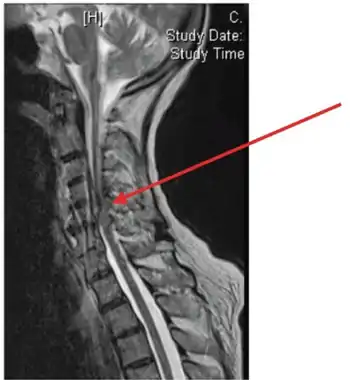

| Image showing epidural abscess (and cord compression) | |

An epidural abscess refers to a collection of pus and infectious material located in the epidural space superficial to the dura mater which surrounds the central nervous system. Due to its location adjacent to brain or spinal cord, epidural abscesses have the potential to cause weakness, pain, and paralysis.

A spinal epidural abscess (SEA) is a collection of pus or inflammatory granulation between the dura mater and the vertebral column.[1] Currently the annual incidence rate of SEAs is estimated to be 2.5-3 per 10,000 hospital admissions. Incidence of SEA is on the rise, due to factors such as an aging population, increase in use of invasive spinal instrumentation, growing number of patients with risk factors such as diabetes and intravenous drug use.[1] SEAs are more common in posterior than anterior areas,[2] and the most common location is the thoracolumbar area, where epidural space is larger and contains more fat tissue.[3] SEAs are more common in males, and can occur in all ages, although highest prevalence is during the fifth and seventh decades of life.[1]